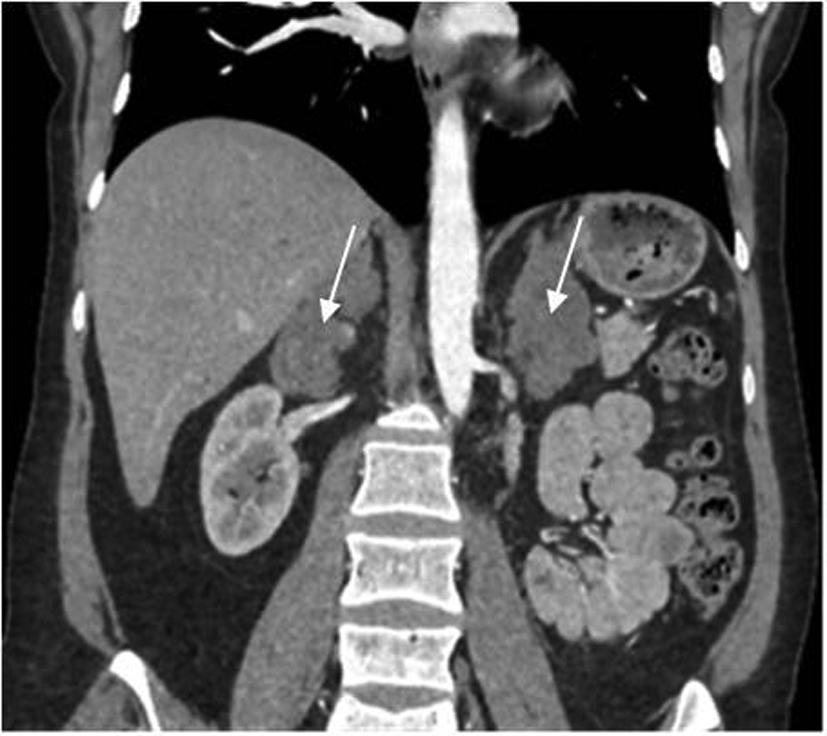

При обследовании в отделении нейроэндокринологии и остеопатий в сентябре 2016 г. у пациентки Ю. был подтвержден АКТГ-независимый эндогенный гиперкортицизм (см. таблицу). В биохимическом анализе крови: калий – 4,5 ммоль/л (3,5–5,1), глюкоза – 4,42 ммоль/л, холестерин – 7,8 ммоль/л (3,3–5,2). В суточной моче метанефрин – 194 мкг (25–312), норметанефрин – 347 мкг (35–445). По данным МСКТ: надпочечники обычно расположены, с четкими неровными контурами. Оба надпочечника деформированы, неравномерно утолщены. Структура неоднородная за счет многочисленных объемных образований округлой и овальной формы, размером от 12 до 36 мм. Наиболее крупные образования расположены в латеральной ножке левого надпочечника (до 33 мм) и в латеральной ножке правого надпочечника (до 28 и 36 мм). Контуры образований четкие, ровные. Структура однородная. Плотность их по фазам составляет: нативная фаза – артериальная фаза – венозная фаза – отсроченная фаза: 13–37–74–38 ед.Н. Размер правого надпочечника (медиальная ножка–латеральная ножка–тело): 12–20–14 мм. Размер левого надпочечника: 18–22–10 мм. Длина правого надпочечника, включая ножки и тело, – 9,3 см, левого – 8,9 см. (рис. 1, 2). При повторной МРТ головного мозга данных за микроаденому гипофиза не получено. Таким образом, был верифицирован диагноз «Синдром Иценко–Кушинга. Первичная двусторонняя макронодулярная гиперплазия надпочечников». Пациентка была консультирована хирургом, показано хирургическое лечение. Из осложнений эндогенного гиперкортицизма подтверждена артериальная гипертензия 2 степени, по поводу чего назначены лозартан, индапамид, доксазозин с достижением целевых показателей АД.

Рис. 1. МСКТ надпочечников пациентки Ю., артериальная фаза, аксиальная проекция (надпочечники указаны стрелками).